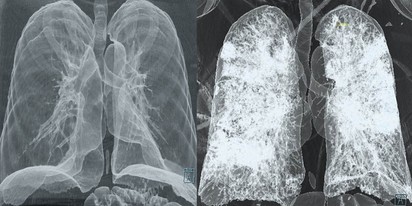

A tüdőszűrés egy mellkasröntgen-vizsgálat, amely a tüdőben és a mellkasi szervekben kialakuló elváltozások, például tüdőrák, tuberkulózis (TBC), krónikus obstruktív tüdőbetegség (COPD) vagy egyéb tüdőbetegségek korai felismerésére szolgál. Magyarországon a tüdőszűrés elsősorban a tuberkulózis szűrésére terjedt el, de a vizsgálat során más tüdőbetegségek jelei is felismerhetők.

A tüdő CT (komputertomográfia) egy speciális képalkotó vizsgálat, amely részletes keresztmetszeti képeket készít a tüdőről és a környező struktúrákról. Ez a vizsgálat jóval részletesebb képet ad, mint egy hagyományos mellkasi röntgen, így pontosabb diagnózist tesz lehetővé számos tüdőbetegség esetén.